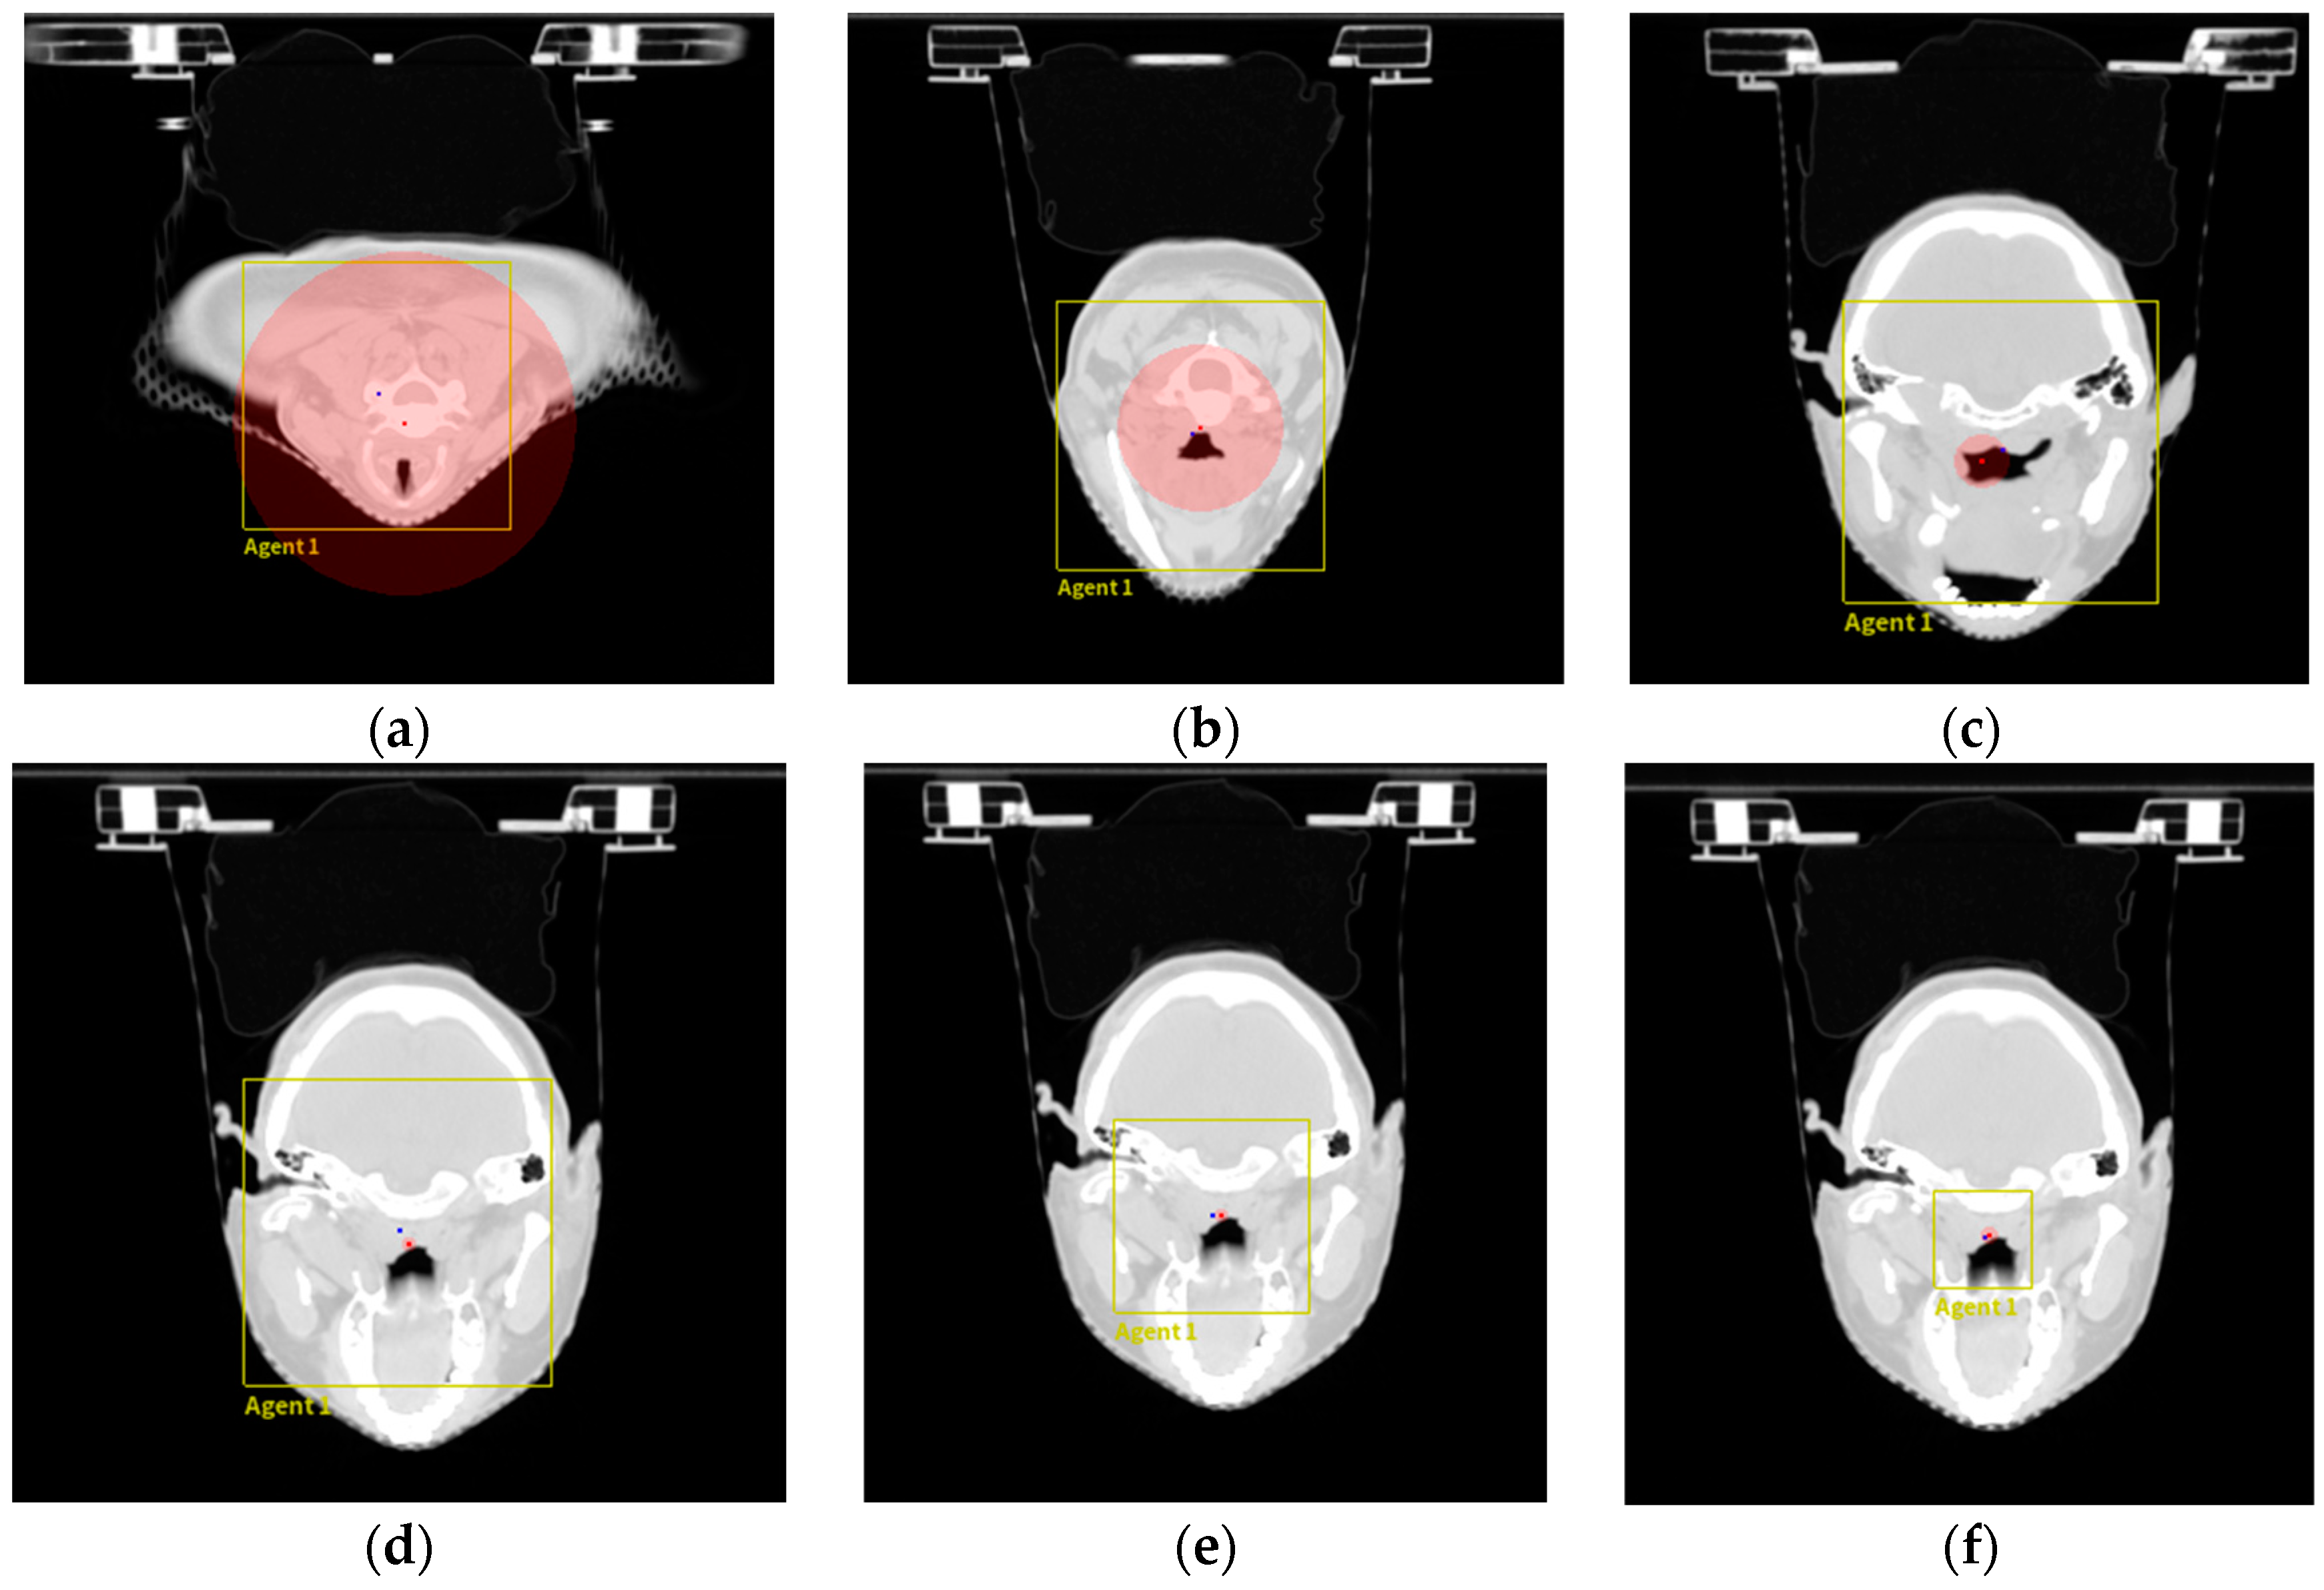

Train: To demonstrate the effectiveness of this work, we conducted experiments on three-dimensional nasopharyngeal carcinoma CT scans and analyzed the experimental results. The experimental process is shown in Figure 3.

The red dots in Figure 3 represent the target feature points, the blue dots represent the agent position, the yellow box represents the search scale size, and the size of the red area around the feature points represents the distance between the agent and the feature points in the z-axis direction. This figure shows the state of the agent search during the training process. From Figure 3a–c, it can be seen that the agent is searching at the maximum scale. From Figure 3d–f, it can be seen that after oscillation occurs (during approaching the target), the agent starts to reduce the search step scale until the minimum scale, and at this point, the agent and feature point positions basically coincide.

Figure 3. Visualization diagram of the experimental process. The figure shows the agent search process. Starting from the starting position after adding prior knowledge, the agent searches at the maximum scale in (ac), oscillations occur in (df), and the agent gradually reduces the search step size to the minimum.